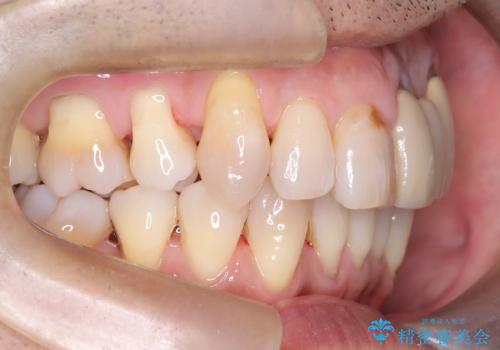

50代からの矯正治療!ブリッジを活かし八重歯を解消

- 50代の患者様で、右上の八重歯と歯並びの乱れを気にされてご来院されました。特に、すでに装着されている前歯のセラミックブリッジを外したくないという強いご希望がありました。精密な検査の結果、八重歯を治すためのスペースが不足しているため、右上の4番目の歯(小臼歯)を抜歯し、そのスペースを利用して歯並び全体を整える治療計画を立案。装置には目立たないインビザラインを採用し、ブリッジを温存しながら八重歯の改善を目指しました。

今回の治療で最も重要だったのは、患者様のご要望通り既存のセラミックブリッジを外さずに矯正を進める点でした。計画通り右上の小臼歯を抜歯し、透明なインビザラインを使用して抜歯スペースを閉じながら、八重歯を正しい位置へ移動させました。ブリッジの形態と調和するに、他の歯の移動を工夫をすることで、複雑な条件をクリア。治療の結果、長年気にされていた八重歯が解消され、見た目が大きく改善しました。50代からでも、ご自身の要望を叶えながら、美しく機能的な歯並びを獲得していただけました。